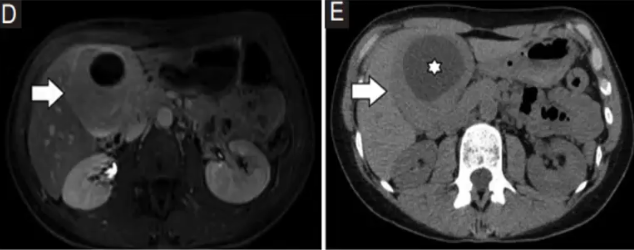

CT表现

❖ 肝内多囊性肿块,具有清晰、厚薄不均或不规则的纤维性囊壁,伴内部分隔、壁结节,偶见囊壁钙化

❖ 平扫时肿瘤的CT密度与水相近(≤30 HU),但因囊内液体成分(浆液性、黏液性、胆汁染色液体)、胆固醇结晶及坏死或脓性物质的存在,不同囊内分隔间的CT值可能存在差异

❖ 增强扫描时,沿囊壁、内部分隔及壁结节/分隔可见强化